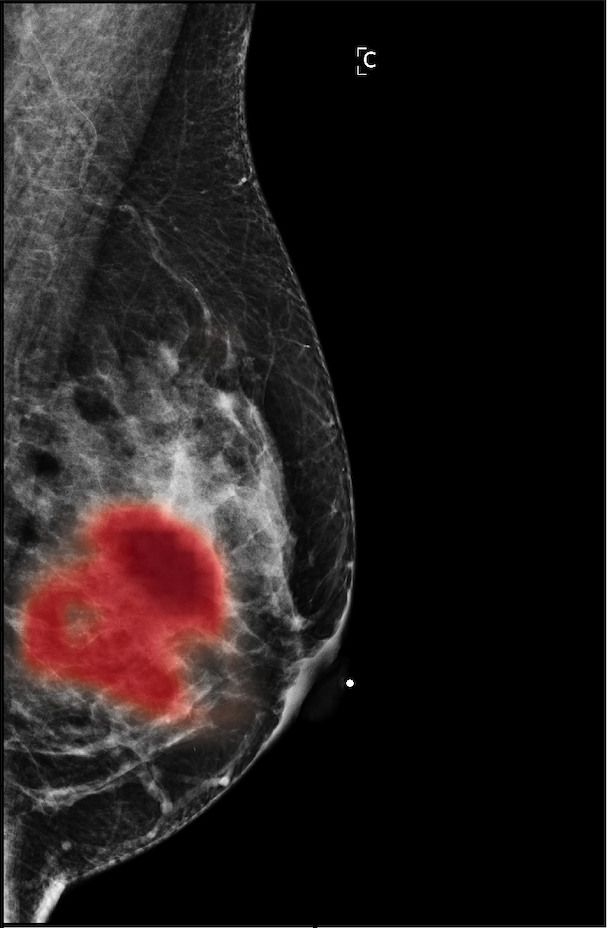

In Figure 7, we visualize saliency maps for four samples selected from the test set. In the first two examples, the saliency maps are highly activated on the annotated lesions, suggesting that our model is able to detect suspicious lesions without pixel-level supervision. Moreover, the attention is highly concentrated on ROI patches that overlap with the annotated lesions. In the third example, the saliency map for benign findings identifies three abnormalities. Although only the top abnormality was escalated for biopsy and hence annotated by radiologists, the radiologist’s report confirms that the two non-biopsied findings have a high probability of benignity and a low probability of malignancy. In the fourth example, we illustrate a case when there is some level of disagreement between our model and the annotation in the dataset. The malignancy saliency map only highlights part of a large malignant lesion with segmental coarse heterogeneous calcifications. This behavior is related to the design of : a fixed pooling threshold cannot be optimal for all sizes of ROI. The impact of is further studied in 3.6. This example also illustrates that while human experts are asked to annotate the entire lesion, CNNs tend to emphasize only the most informative regions. While no benign lesion is present, the benign saliency map still highlights regions similar to that in the malignancy saliency map, but with a lower probability than the malignancy saliency map. In fact, calcifications with this morphology and distribution can also result from benign pathophysiology [42].